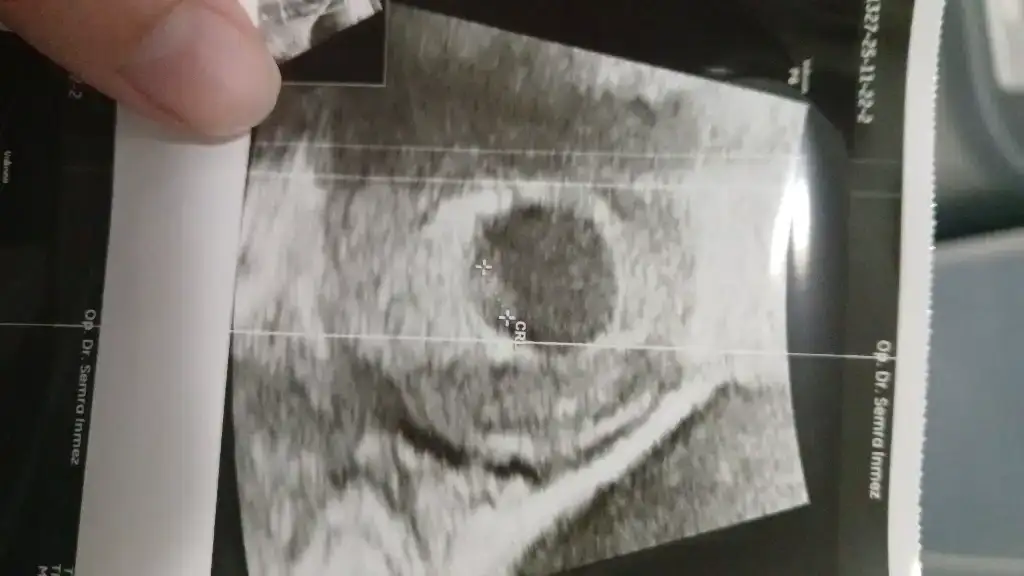

Hcg 138 ile öğrendim 4 kasımda. 5+3 te kedeyi gördüm, 6+3 te bebegi ve kalp sesini hissettik

Kızlar cinsiyet tahminlerinizi alayim ve de masallahlari tabi